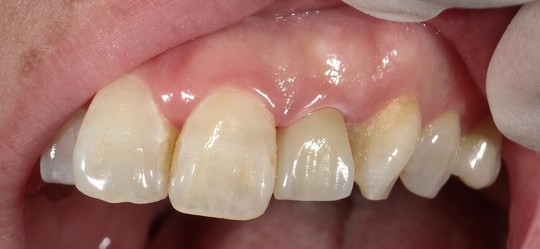

年齢:50代女性

治療内容:左上真ん中から2番目の歯で、他院様での修復物不適合で見た目を気にされてご相談を受けました。e.maxクラウンの審美修復で、ご自身の歯に近い自然で美しい見た目に仕上がりました。

治療期間/通院回数:3回

費用: e.max クラウン 110,000円 ※2025年7月現在の価格